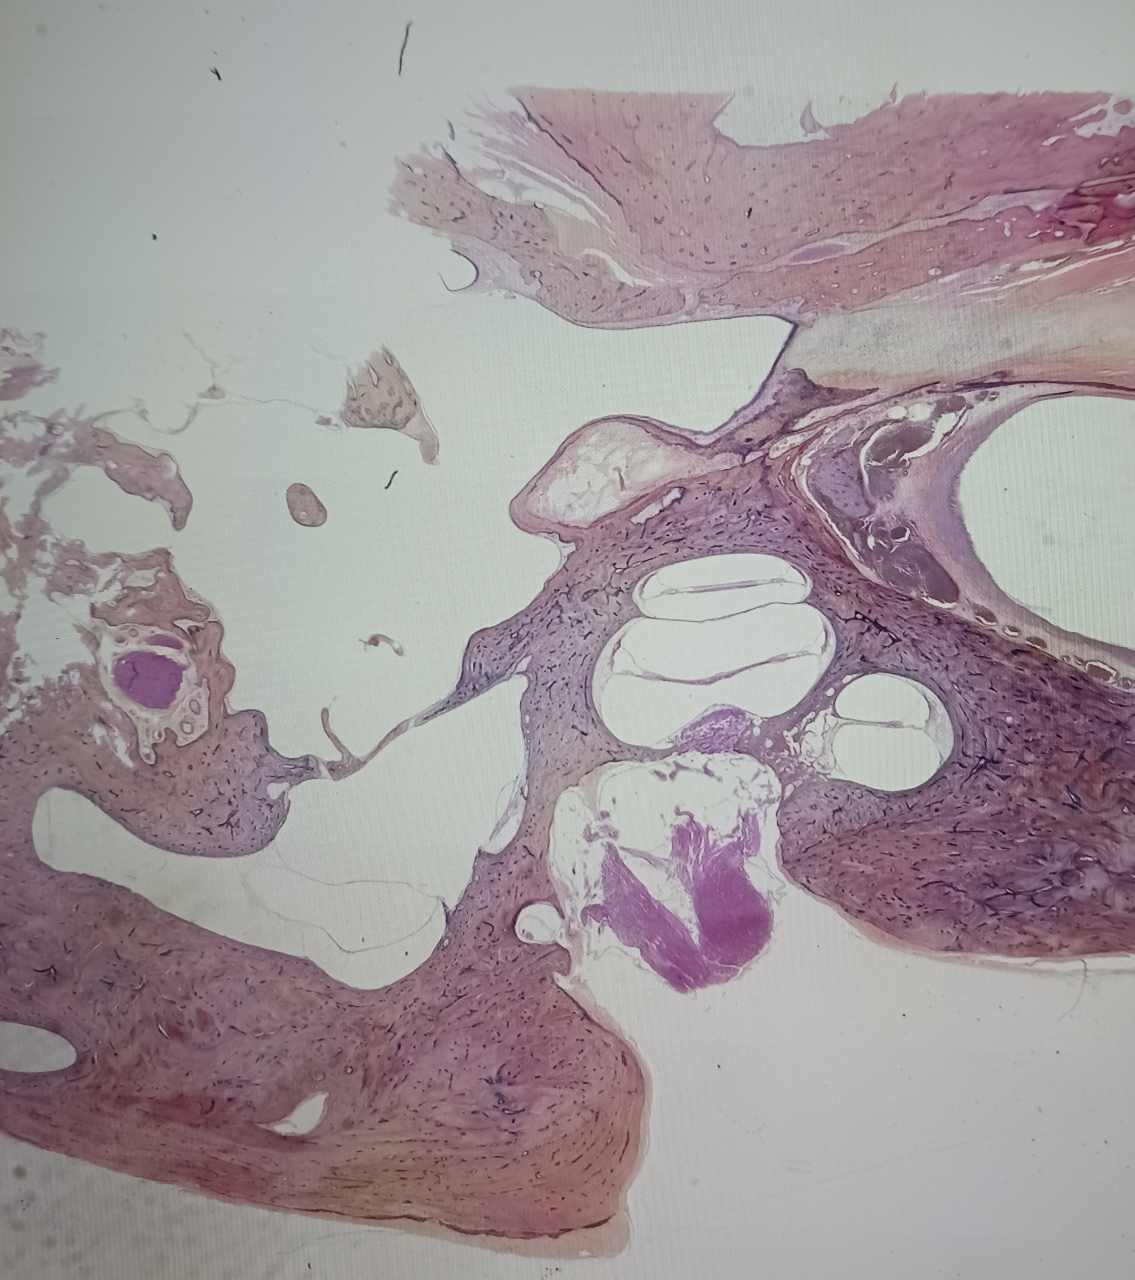

In the early 20th century, Otology (ENT) Departments across the United States established temporal bone histopathology laboratories.

These innovations were inspired by European prototypes and became integral to understanding the anatomy and physiology of the human ear.

The Labyrinthine Archival Restoration Project-NFP is a non-profit dedicated to analyzing, digitizing, and restoring the archival collections of these University laboratories.

Our goal is to ensure that these precious resources continue to serve educational & research purposes.